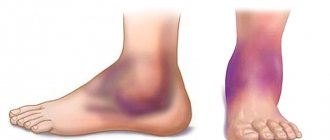

Гангрена проявляет себя появлением синюшных очагов на пальцах стоп или пятках, впоследствии приобретающих черный цвет. Очаги имеют тенденцию к распространению, слиянию, вовлечению в процесс проксимальных отделов стопы и голени.

Традиционно выделяют сухую и влажную гангрену. Основное их различие – в отграниченности (демаркации) участка некроза от других тканей. При сухой гангрене имеется участок черной кожи, четко отграниченный от окружающих неизмененных тканей, не имеющий тенденции к распространению. Общее состояние пациентов при этом не страдает (за исключением сохраняющихся болей), нет признаков интоксикации, отсутствует гипертермия. Такой тип гангрены при небольшом участке поражения (например, сухая гангрена дистальной фаланги пальца стопы), можно длительное время вести консервативно, не выставляя показаний к операции, в отдельных случаях возможно самоотторжение некротизированного участка. Поспешность с операцией в такой ситуации, за счет операционной травмы может вызвать прогрессирование некротического процесса.

При влажной гангрене демаркация отсутствует, на стопе имеются участки как черного, так и синюшного цвета, проксимальнее очага некроза кожа гиперемирована, из-под некрозов имеется гнойное отделяемое с неприятным запахом. Имеются признаки интоксикации (жажда, тахикардия и др.), гипертермия до субфебрильных и фебрильных значений. Влажному процессу свойственно быстрое прогрессирование, с распространением некроза в проксимальном направлении.